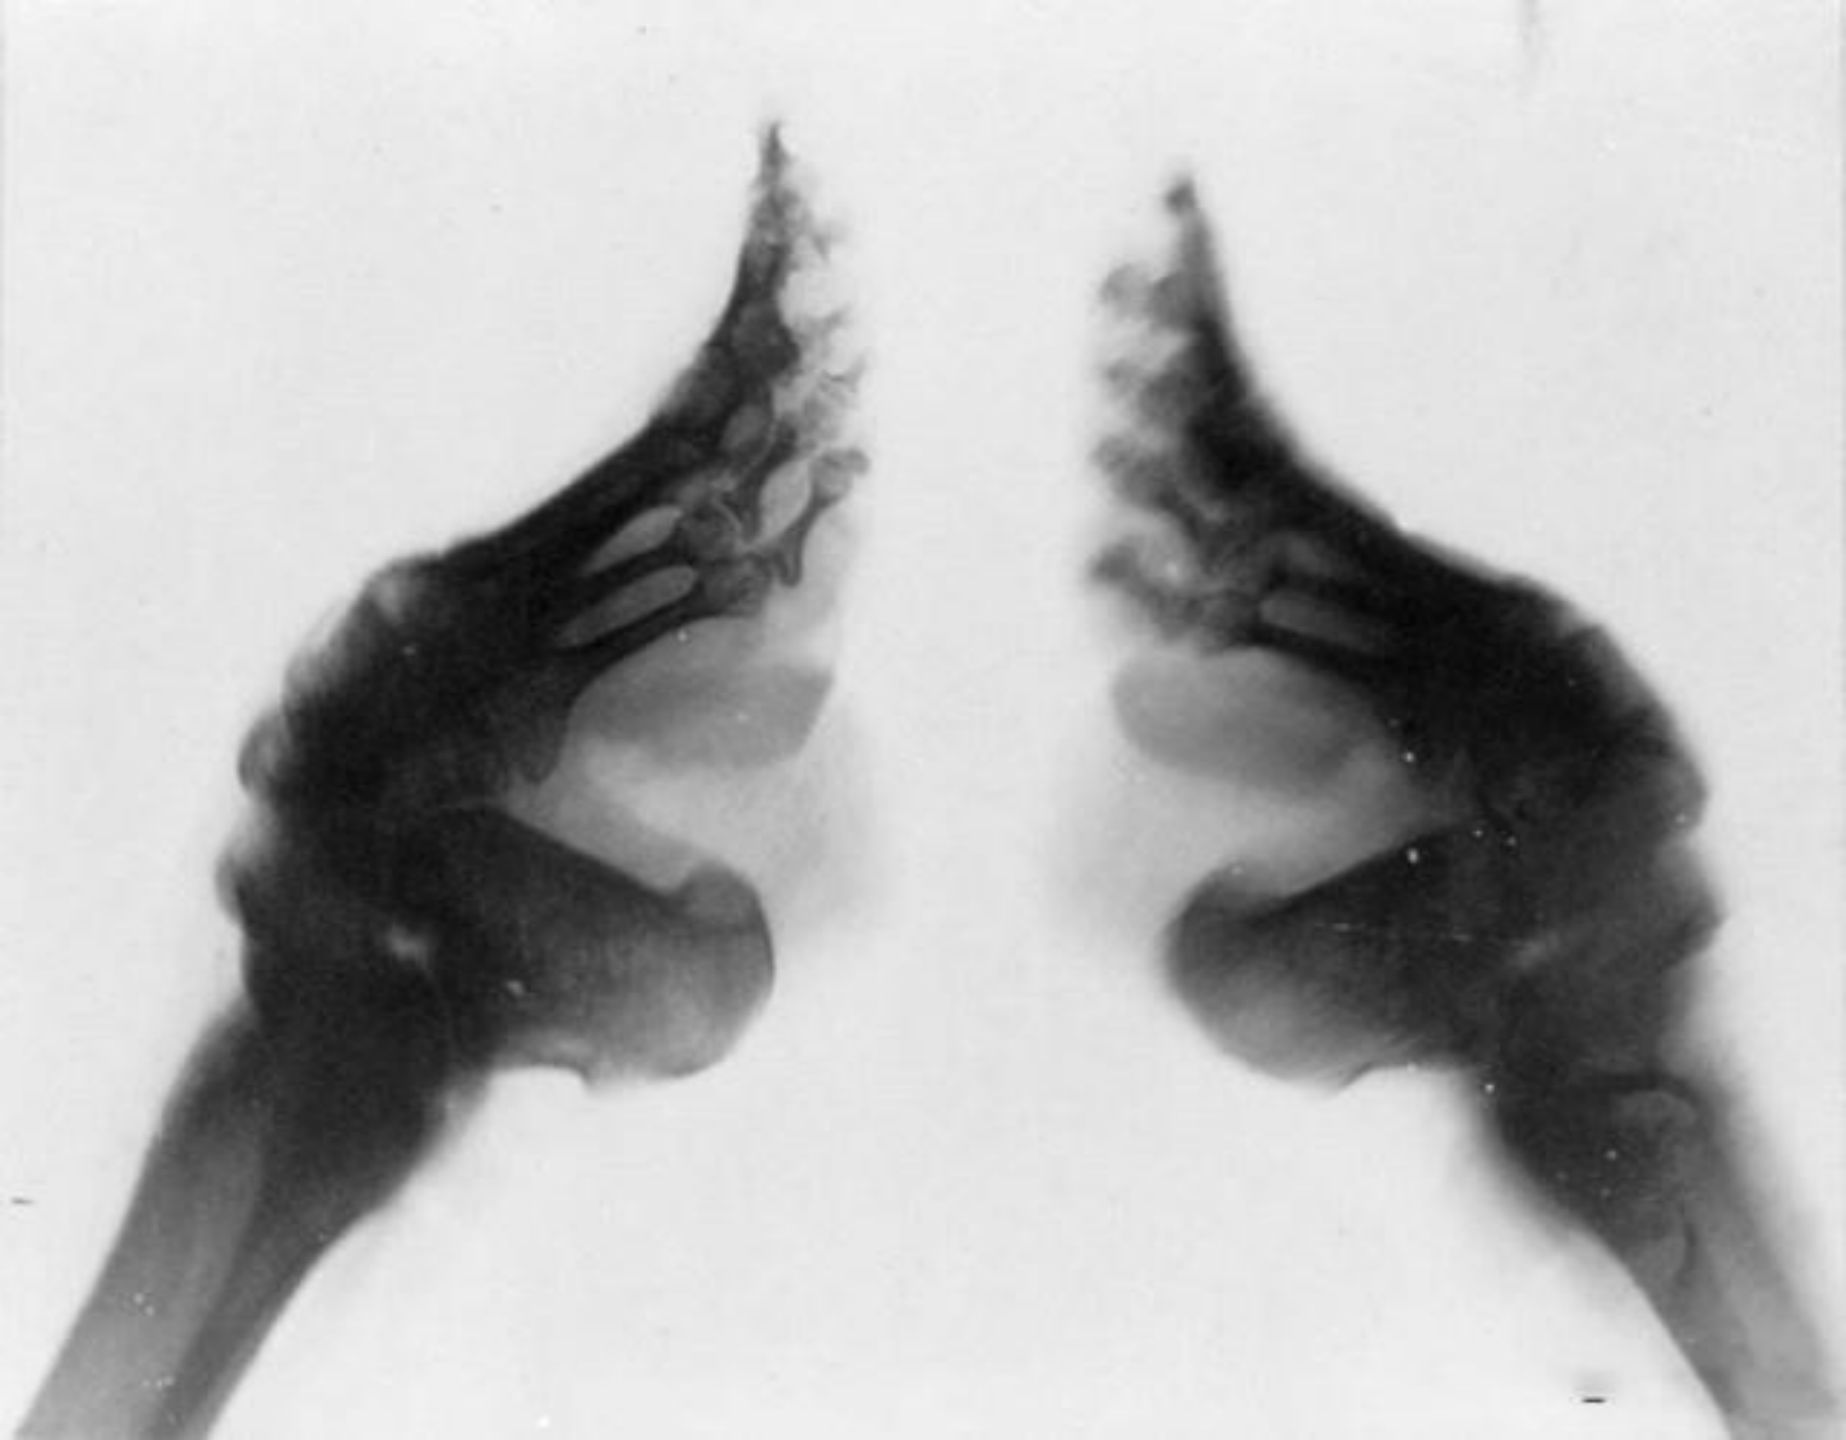

世界上有哪些令人震惊的陋习?934 / 作者:一夜雨十年灯潞 / 帖子ID:96674

X 光片下的变形骨头